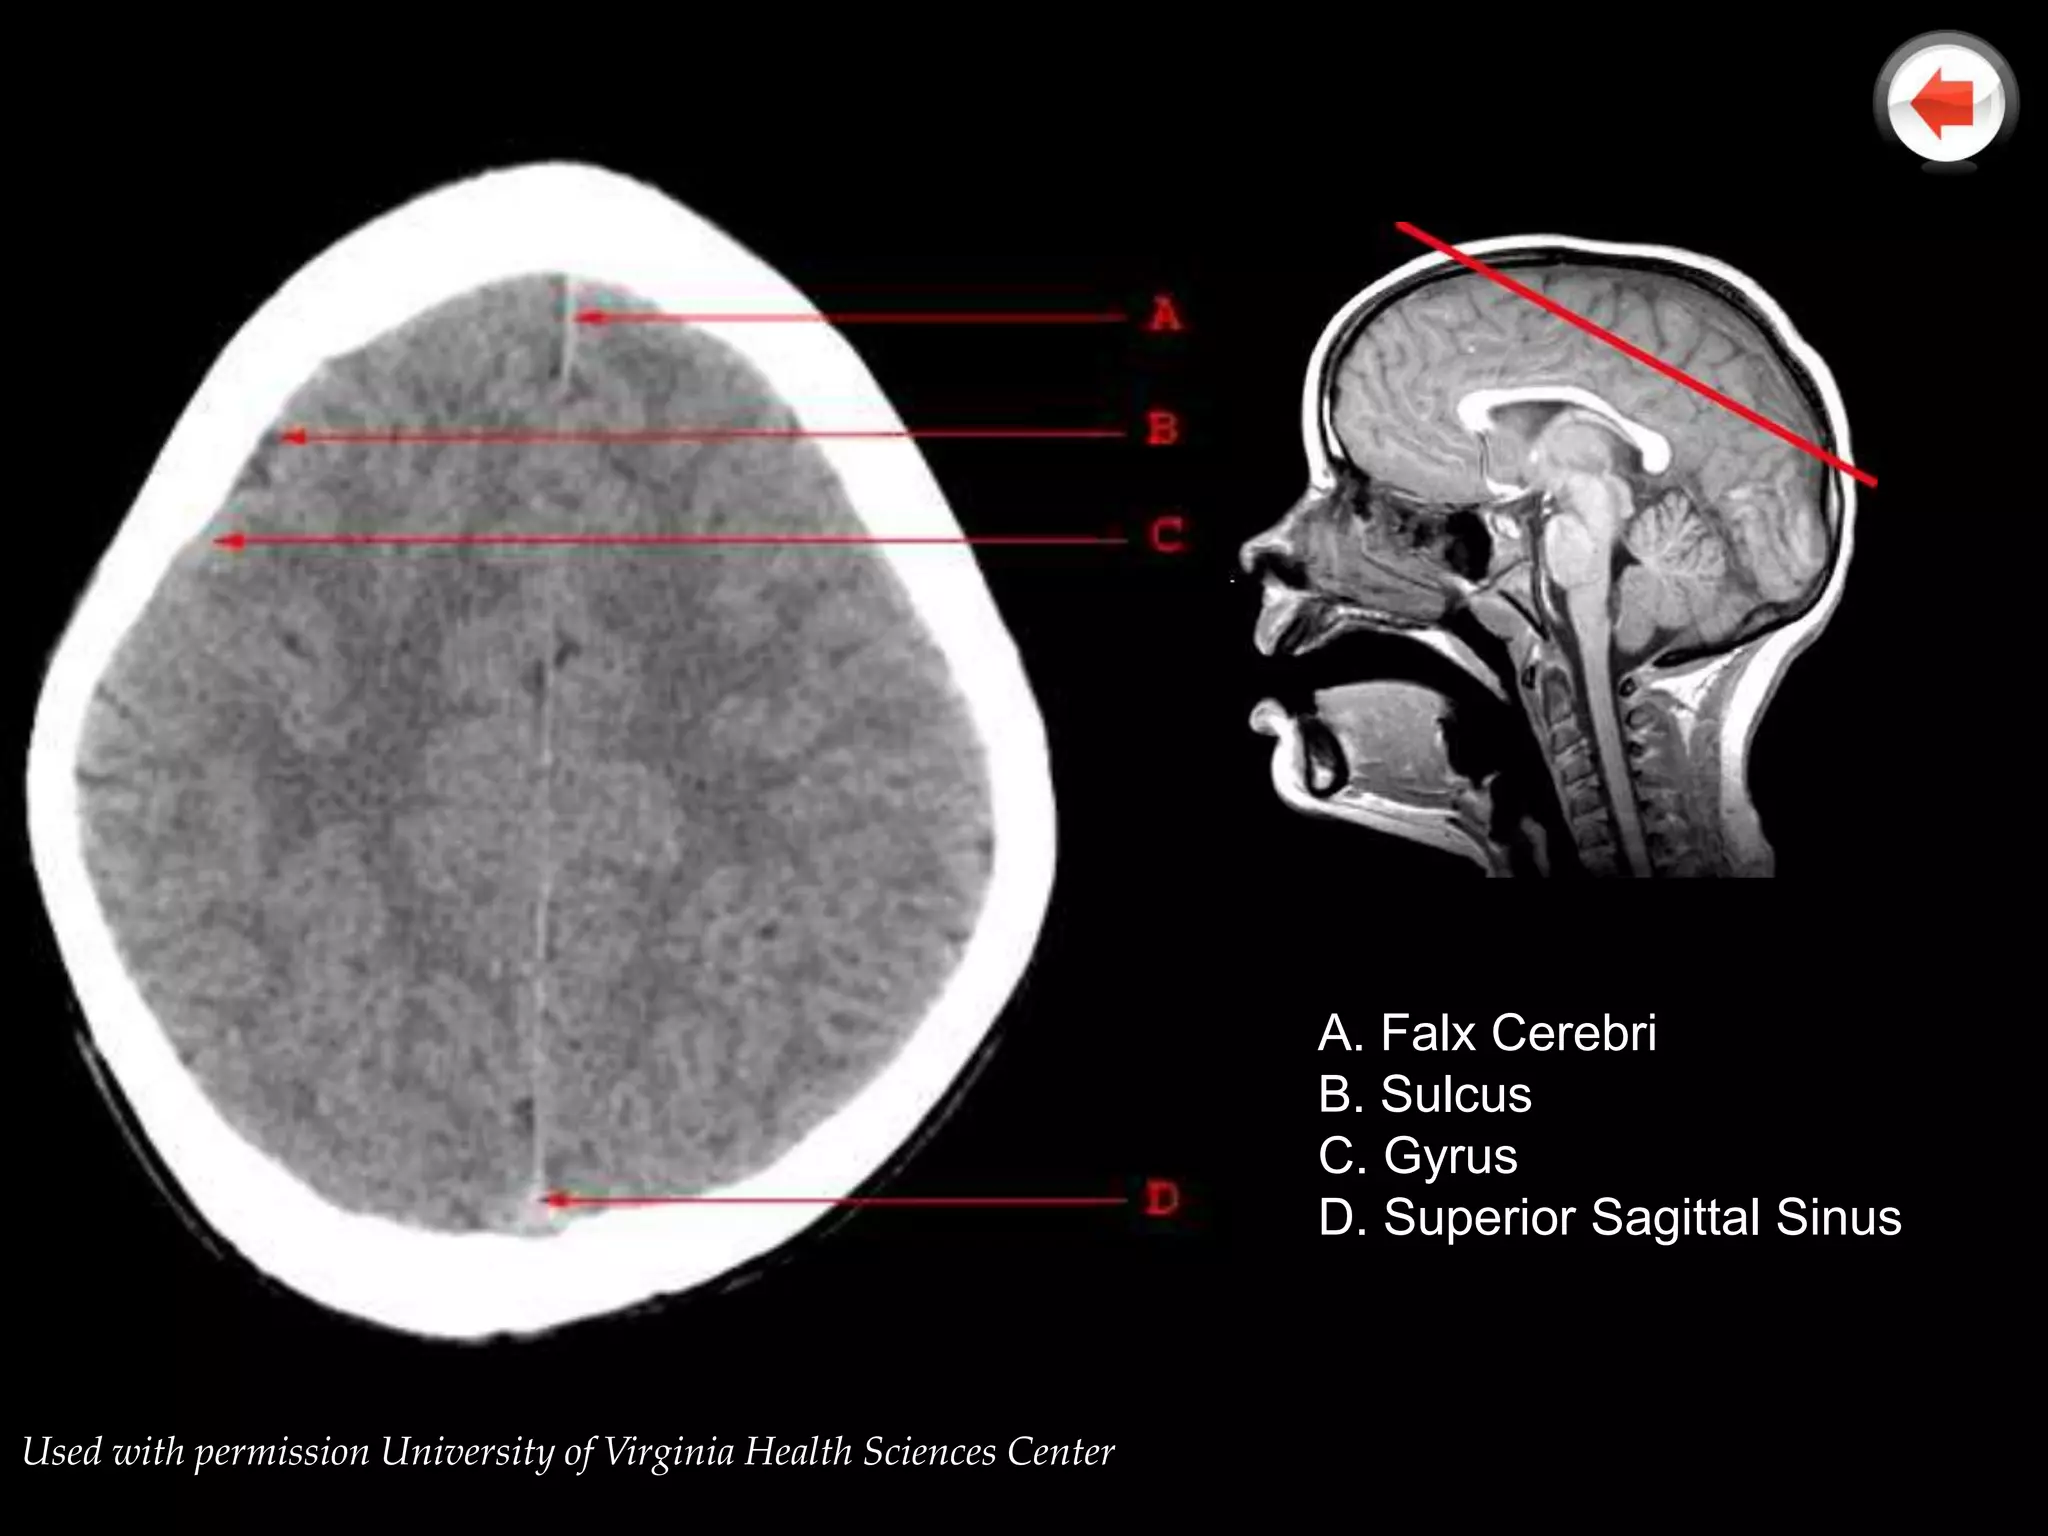

A. Falx Cerebri

B. Sulcus

C. Gyrus

D. Superior Sagittal Sinus

Used with permission University of Virginia Health Sciences Center